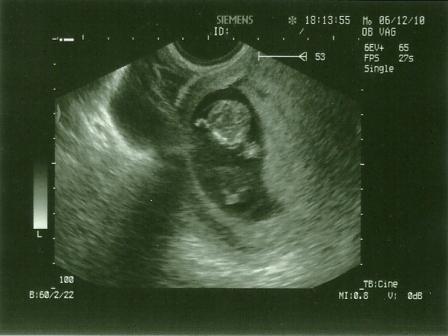

A képen kicsit takarja az arcát, de szerencsére mindent rendben talált nála ma Sz.!!!! :)

Nagyon szégyellőske - hát ebből a szempontból tuti nem az apja vére! :) - úgyhogy egyelőre nem lehet 100%-ra kijelenteni Róla, de a mai napon látottak alapján Sz. szerint úgy tűnik KISLÁNYUNK lesz! :) A következő vizsgálaton már nagyobb eséllyel láthatja majd, azt mondta....

Legközelebb majd a 20. héten kell mennünk, ami már átcsúszik január elejére, akkor lesz a 2. genetikai uhu .... de sebaj, mert 17-én még egyszer randizunk Vele majd 4d-n...kíváncsi leszek ott mit fogunk látni!? :)

Nagyon jó volt hallani, hogy minden rendben, hú gyerekek, már egész emberformájú, tényleg!!!..... Amúgy ma a megszokottól eltérően teljes nyugalomban mentem a dokihoz .... :)

Szóval a képen fentről lefele haladva (gyk. direkt befordítottam mert egyébként fekvő lenne a kép.... :)....)

legfelül a homloka

alatta a két szeme közte az orra

alatta a szája amit takar a kezével.. ott azok a vonalkák az ujjacskái!!!

látszik még a hasa az a nagy kerek a szélén világosabb kontúrral

annak a jobb és bal oldalán pedig a karjai halványabban

ezen a képen a lábai nem látszódnak bár azok is felhúzott összezárt állapotban voltak szinte végig :)